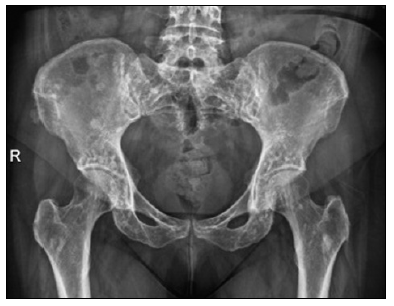

Descripción del caso: El primer caso filiado fue en una mujer de 52 años, a la que se realiza radiografía de pelvis y de manera casual su traumatólogo observa las lesiones osteocondensantes (Figura), por cuyo motivo fue remitida a la Unidad Metabólica Ósea donde se completa el estudio, siendo diagnosticada de osteopoiquilia.